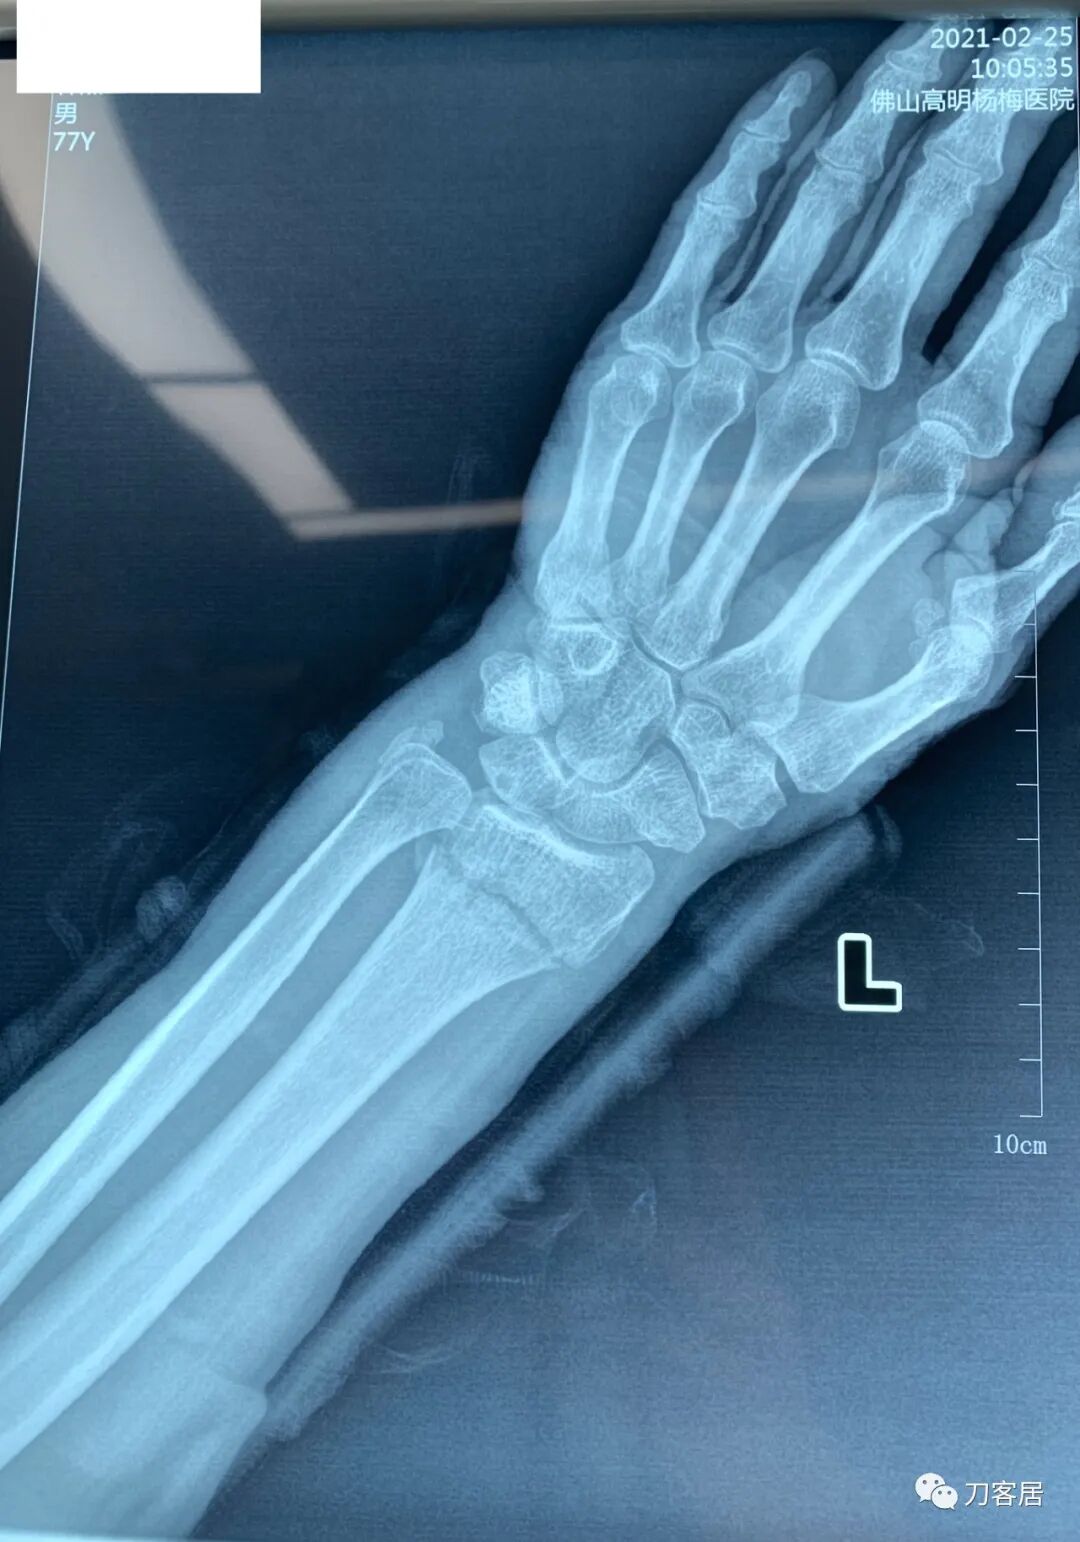

下面是这个6岁孩子,尺桡骨远端双骨折的术前及术后片子和外观照片。

1.  这是一个很简单的6岁儿童无移位的尺桡骨远端骨折。没有皮肤损伤,没有移位,没有骨折碎块儿。

2.  这个骨折处理起来也很简单,单纯的打石膏托或者中医的小夹板,或者正规的包括腕关节和肘关节的管型石膏外固定4周即可治愈该骨折。实在不行,如果这个孩子比较听话,不太调皮的话,用一本书,一个三角巾悬吊固定4周,都可以治愈该骨折。但是给这个患者用外固定架做了手术,而且桡骨远端的几颗克氏针距离骨折线太近,其中一枚克氏针进入到骨折间隙内。从这个术中图片来看,术者的外固定手术技术也有待于进一步的提高。毕竟术者应该还很年轻。从X线片来看,前臂及手的尺侧有不透光影,应该还使用了外固定石膏绷带托,而且我猜测应该是高分子的石膏绷带托,这个是纯属猜测,不一定是对的,不过如何解释前臂尺侧的不透光影呢?如果真是用了石膏绷带外固定的话,那为啥要做手术呢?外固定架术后就不该再用石膏绷带托辅助了。